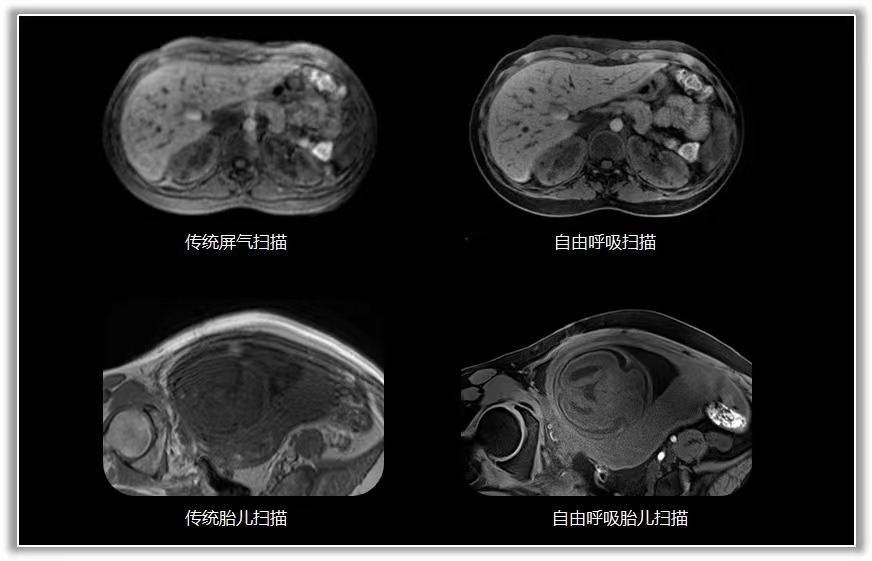

传统的磁共振成像对运动非常敏感。为了在体部获得有价值的诊断图像,扫描前都需要给患者佩戴呼吸门控装置,对患者进行呼吸训练,而且扫描中还要求患者多次屏气扫描。

而大量的重症患者、老年人和小孩都无法有效配合进行呼吸训练和屏气扫描,给成像带来了困难。

MAGNETOM Vida 3.0T磁共振配置了生命矩阵系统,这就使磁共振犹如具备生命一般,患者一躺上扫描床,磁共振就能真切地感受到患者解剖、呼吸、磁场等人体信息。在扫描过程中,无需患者刻意配合,无需佩戴任何呼吸门控装置,全程自由呼吸就可完成扫描,获得高质量的检查结果。

因此,重症患者、老年人和小孩患者群体也能舒适地进行扫描。